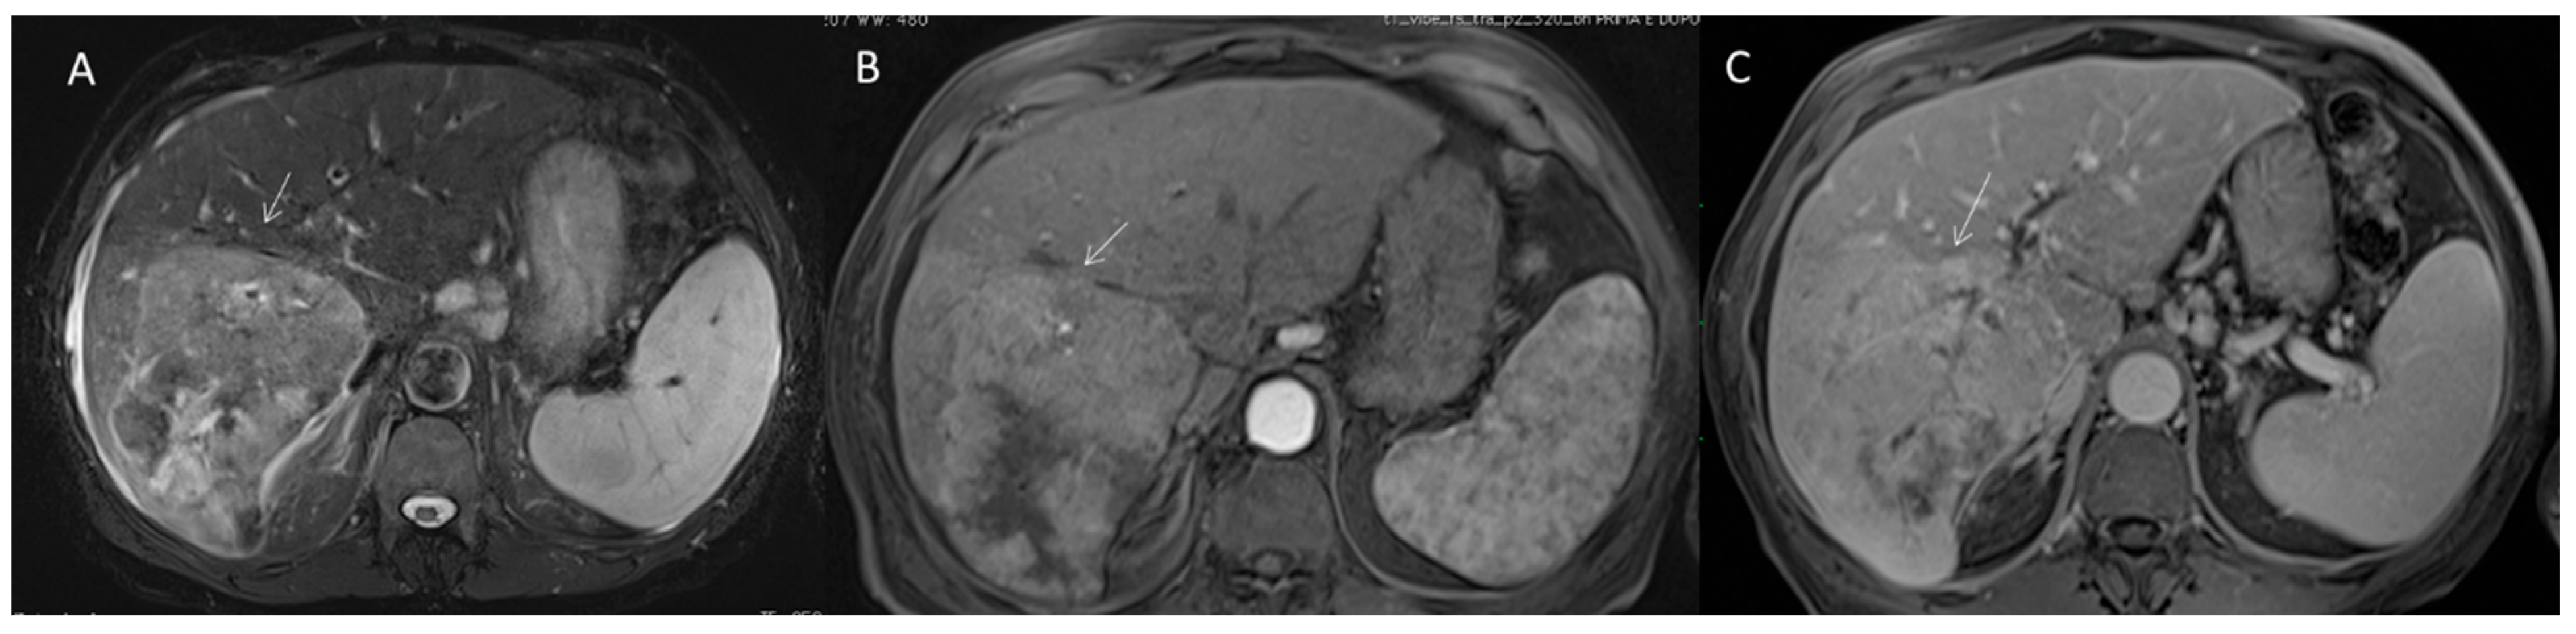

2.2.3. HCC Diagnosis

2.2.4. Ancillary Features

2.2.5. LR-M Category